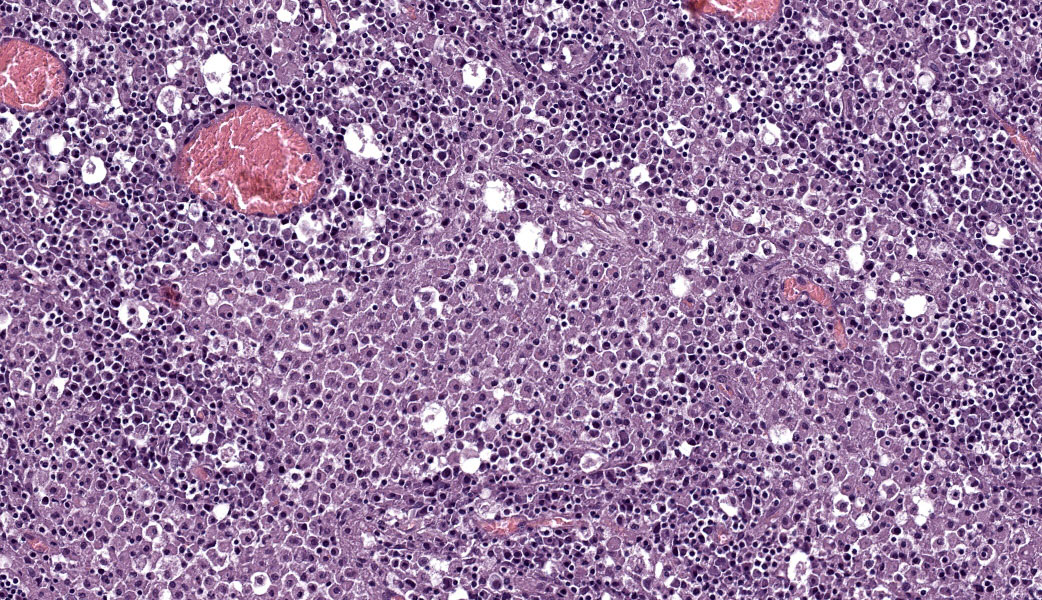

Microscopic Description:

Abdominal lymph node: Multifocal, severe cellular infiltrates with undefined margins are randomly distributed within the lymph node parenchima especially in the subcapsular areas. They extend into the serosal expanding and effacing the mesothelial lining. The infiltrates are characterized by a severe mixed inflammatory population with largenumbers of both viable and lytic neutrophils surrounded by occasional large macrophages with abundant cytoplasm and rare lymphocytes and plasma cells. In the center of almost each infiltrate the neutrophils population shows karyolysis, pyknosis, karyorrhexis and the accumulation of extensive amount of amorphous eosinophilic, proteinaceous material admixed with cellular debris (lytic necrosis).

Immunohistochemical (IHC) staining of lymph node sections using a mouse anti-Feline Coronavirus antibody (clone FIPV3-70 Serotec, Oxford UK) demonstrates strong positivity for many elements within the inflammatory infiltrates, suggestive of presence of viral antigen.

Lymph node: Lymphadenitis and capsulitis, necrotizing and granulomatous, chronic, multifocal to coalescing, marked, with paracortical hyperplasia.